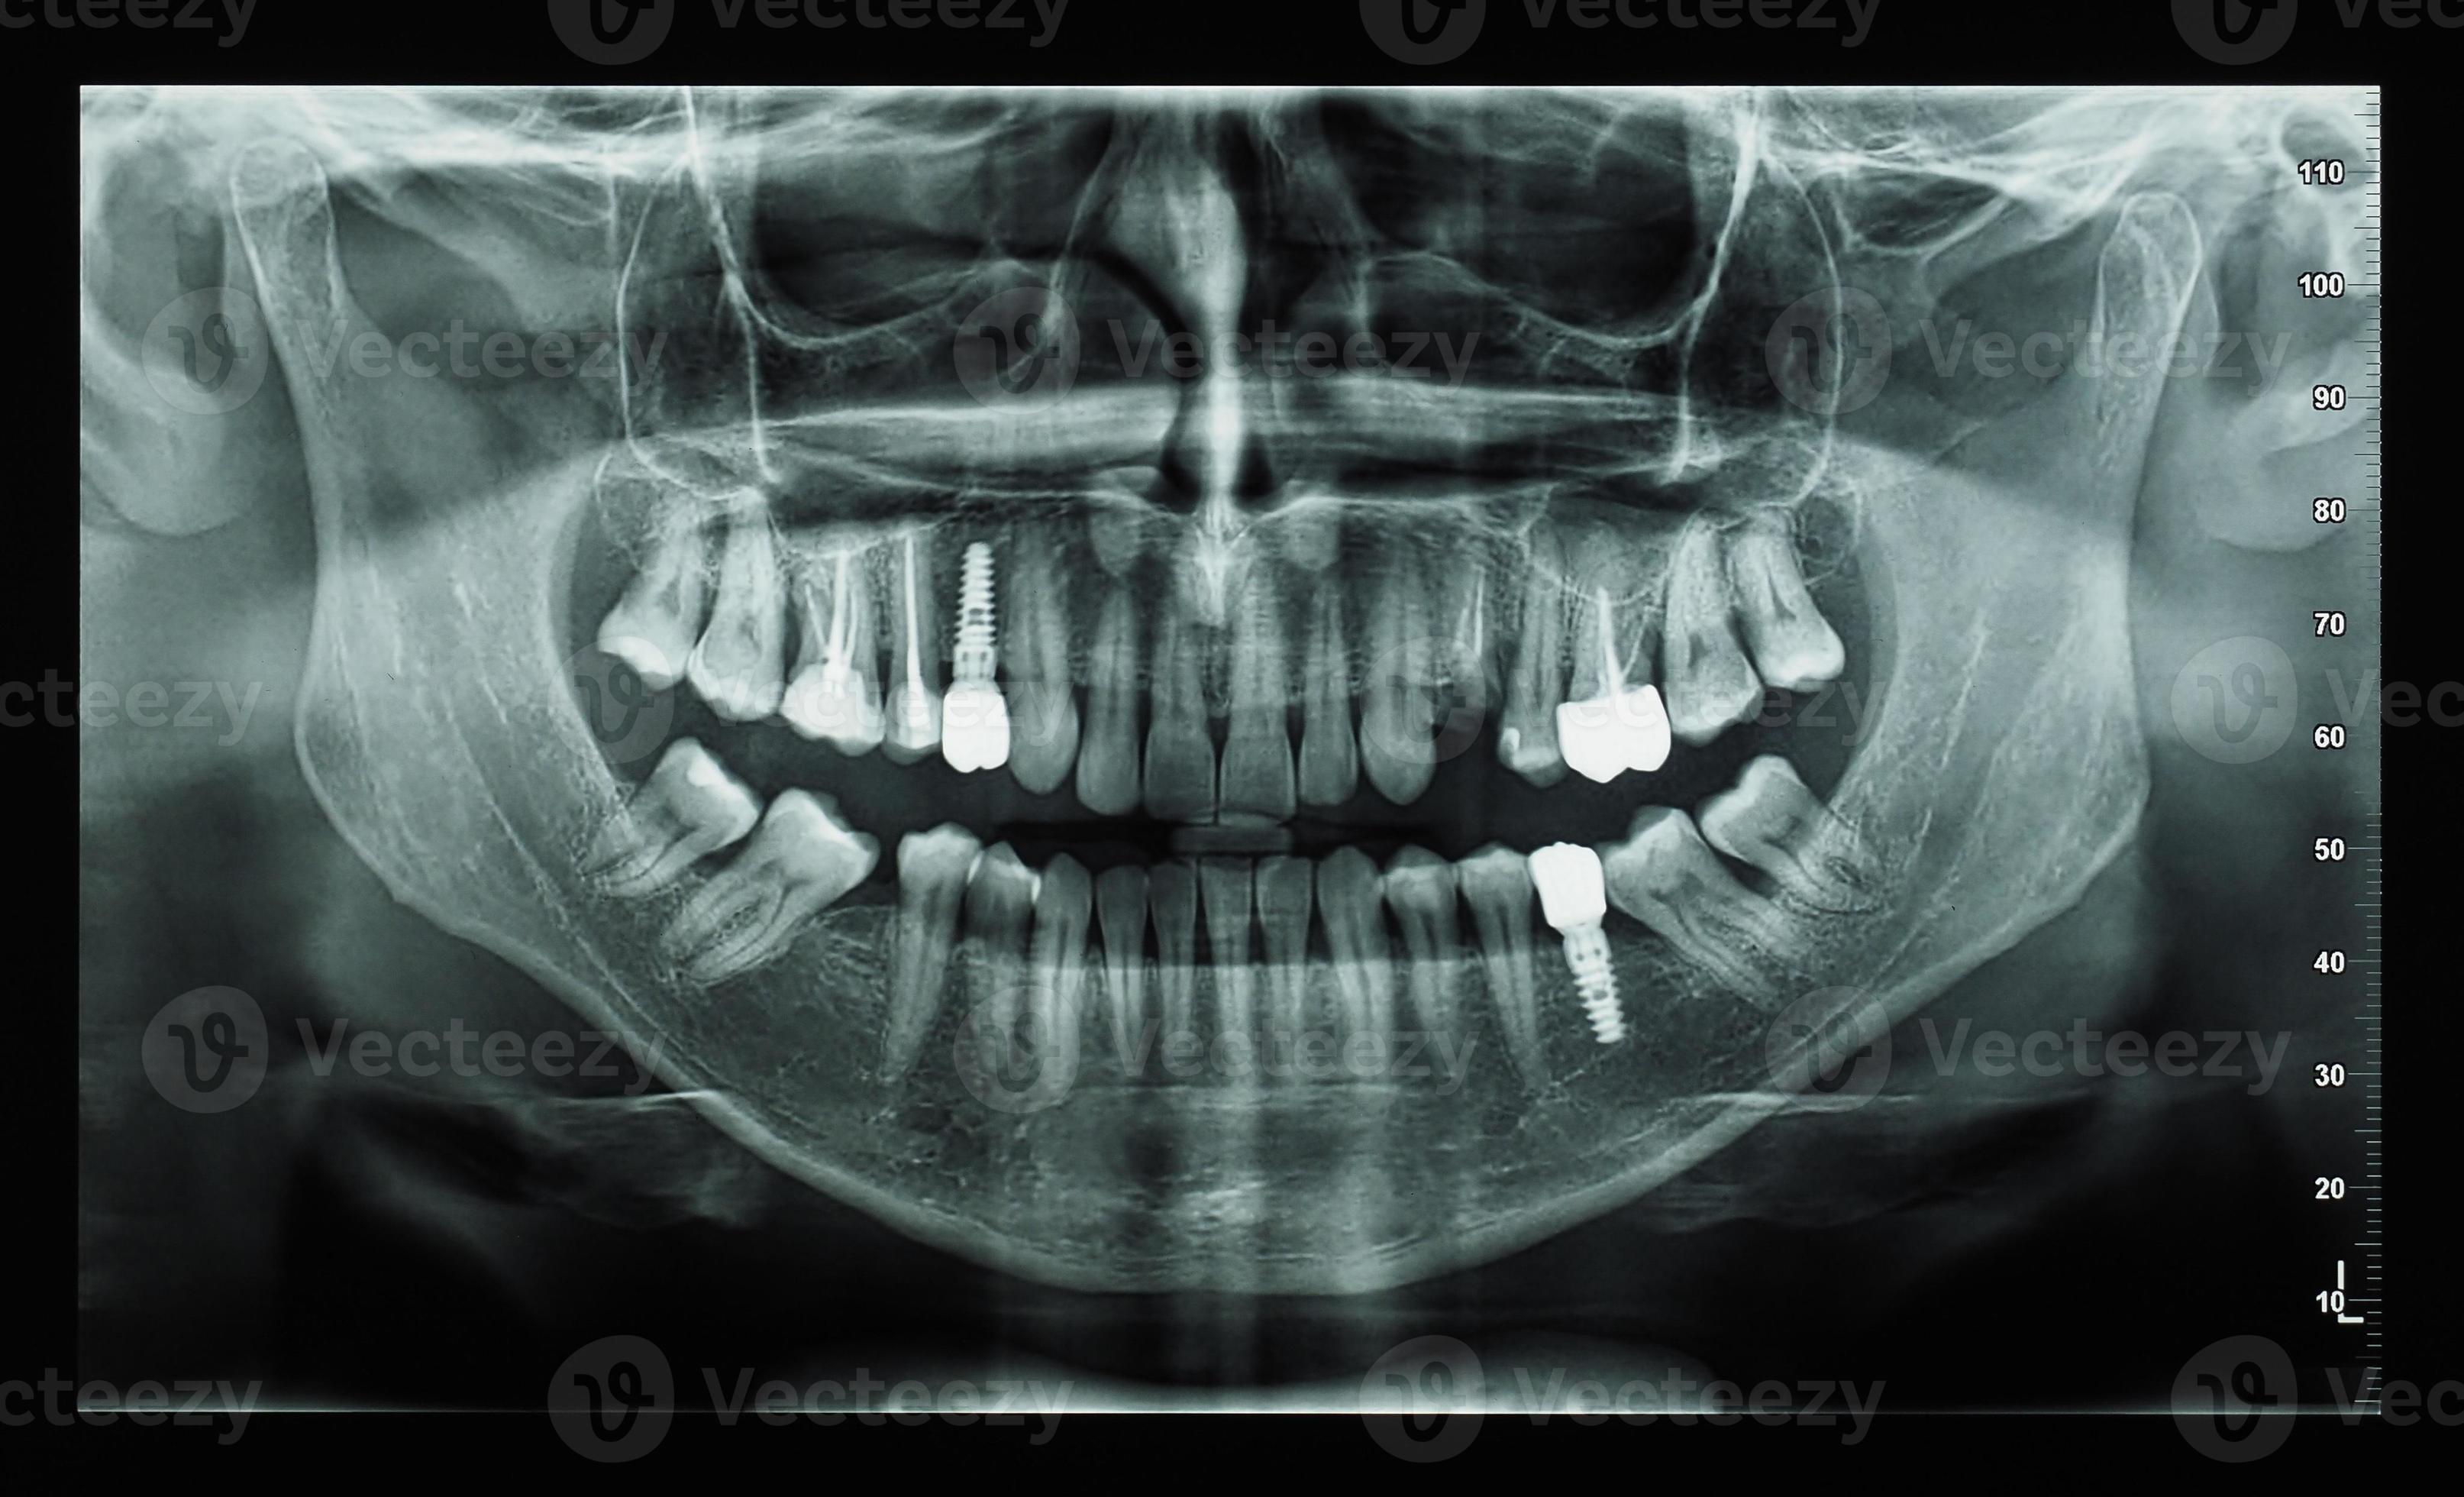

From www.vecteezy.com

orthopantomograph panoramic image radiograph of teeth 9845733 Stock What Is A Radiograph Of Teeth This helps your dentist spot problems like cavities between teeth, impacted teeth, or jawbone damage that they can't see during a regular exam. Dental radiographs can broadly be divided in to two categories: Cavities, infections, and other conditions show up as dark spots on the lighter image of the tooth. Dental radiographs work by using a small, controlled burst of. What Is A Radiograph Of Teeth.